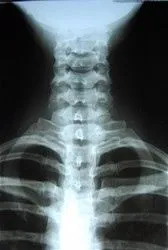

X-Ray

xray.jpg X-rays are often taken on most patients to give the doctor an inside look at what is going on with the bone structure of the entire spine and surrounding skeletal structure. From this x-ray, the doctor can tell your current spine angles as well as any potential further issues including the potential for additional information such as an MRI.